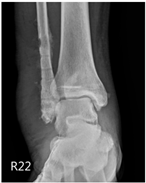

Patient A was a 70-year-old female with a right distal tibiofibular fracture and underwent ORIF in March 2020. There were no known comorbidities for Patient A. One year after ORIF, she began to develop recurrent bullae formation of the right foot, accompanied by tenderness around her operative wound. Neuromuscular function and range of motion were intact, but a local skin rash and bullae formation with hyperpigmentation were observed. The white blood cell count was within the normal range at 3739/μL, which reduced the possibility of FRI. A biopsy of the skin lesion from Patient A was evaluated for pathological examination (Figure 1). The lesion showed psoriasiform dermatitis changes. The epidermis demonstrated acanthosis, hyperkeratosis, parakeratosis, and spongiosis. There were alternating zones of hypo- and hypergranulosis, elongation of rete ridges, and thinning of suprapapillary plates. Neutrophils and lymphocytes infiltrated the epidermis and around blood vessels in the dermis, but eosinophils were rarely seen, which was less typical of an allergic reaction. However, delayed-type hypersensitivity (type IV) was suggested given the chronic 2-year course, manifestations without pus or highly elevated white blood cell counts, and a biopsy-proven predominant presence of neutrophils and lymphocytes. A topical corticosteroid was prescribed to manage the symptoms, but only a slight improvement was observed. Based on her medical history, as well as physical and pathological examinations, a diagnosis of contact dermatitis due to suspected hypersensitivity to the titanium alloy in osteosynthesis was suggested. Radiographs showed bone unions, and fixation with the titanium alloy was no longer necessary. Therefore, she underwent plate and screw removal in March 2023. The symptoms of allergy were resolved after implant removal following confirmed bone unions.